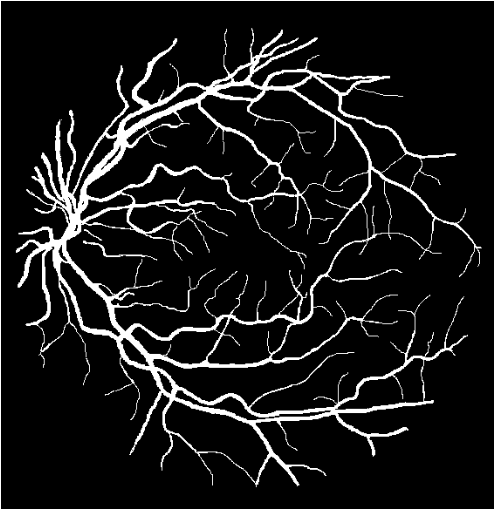

The CNN was trained and tested against the Digital Retinal Images for Vessel Extraction (DRIVE) database111http://www.isi.uu.nl/Research/Databases/DRIVE/, a standardized set of fundus images used to gauge the effectiveness of classification algorithms [24]. The images are 8 bits per RGBA channel with a 565584 pixel resolution. The data set comprises of 20 training images with manually delineated label masks and 20 test images with two sets of manually delineated label masks by the first and second human observers, as shown in Fig. 1. The images were collected for a diabetic retinopathy screening program in the Netherlands using a Canon CR5 non-mydriatic 3CCD camera with a 45° field of view [24].

The output of PixelBNN is a binary label mask, predicting vessel and non-vessel pixels thereby segmenting the original image. Each dataset contains a two experts’ manual delineations; the first was used as the ground truth for training the model and the second was used for evaluating the network’s performance against a secondary human observer. Independently, each dataset was used to train a separate model from scratch resulting in three sets of model parameters.